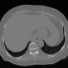

4D CT. DIR-LAB [2] thoracic image dataset for DIR that inlcudes inspiratory and expiratory breath-hold CT image pairs were used for training. Although large permutations are possible, only breathing cycles 00-50, 10-80 and 30-90 were considered from 10 different sets (a total of 120 volumes). As a consequence we avoid an imbalance in the training dataset as most of the breathing cycles did not present strong deformations. For testing the POPI [9] lung dataset was used. The provided segmentation for air, body and lungs were used for evaluation.

3.2 Registration of 4D CT data

Conv2Warp has been evaluated by comparing it to the DIR state-of-the-methods. We also provide results where we restrict the convolution blocks in the Conv2Warp model to linear convolution only (ConvNet). For both these architectures, we will compare them only for Catmull-Rom spline based interpolation as it outperformed other spline techniques in our experiments. Seven pairs of different breathing cycles of 4D-CT data [9], each with 141 slices, where improvement of DIR methods compared to pre-alignment were significant are shown in Table 1. While the accuracy of our method measured by Dice (.90) and Jaccaard coefficient (.84) is similar to the rigorous simpleElastix (SE111http://simpleelastix.github.io), the run time is reduced by a factor of 141. Conv2Warp outperforms all other state-of-the art methods and ConvNet for almost all considered pairs. The test time on CPU is nearly 2.94 s which is multiple-folds lower than conventional DIR methods. Our model is light weight with inference time on a GPU of less than 1 s.